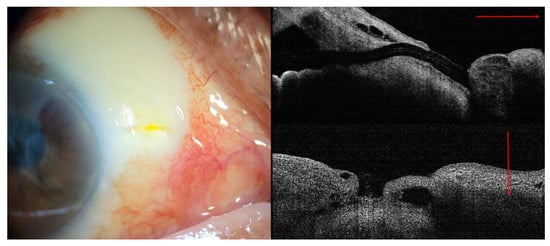

During the follow-up period, the hypovascular bleb gradually changed into an avascular bleb. Periocular pain and tearing developed 18 months after the initial operation, with mild deterioration of visual acuity from 20/50 (LogMAR 0.4) to 20/100 (LogMAR 0.7). Slit-lamp examination revealed a small defect in the conjunctiva, corresponding to the exit point of the XEN. The Seidel test result was weakly positive; however, the patient’s IOP remained acceptable at 15 mm Hg and there was no evidence of blebitis (Figure 3).

Figure 3. Slit-lamp examination and AS-OCT revealed the XEN gel stent exposure with small conjunctival defect due to conjunctival erosion (red line: linear scan on AS-OCT).